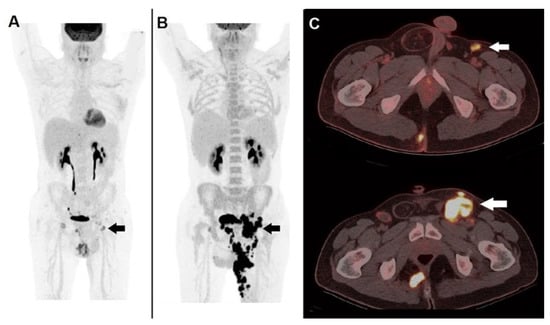

- Holtkamp, L.H.J.; Chakera, A.H.; Fung, S.; Stretch, J.R.; Saw, R.P.M.; Lee, K.; Ch’ng, S.; Gonzalez, M.; Thompson, J.F.; Emmett, L.; et al. Staging 18F-FDG PET/CT Influences the Treatment Plan in Melanoma Patients with Satellite or in-Transit Metastases. Melanoma Res. 2020, 30, 358–363. [Google Scholar] [CrossRef]

| Holtkamp et al. [22] | 2020 | Prospective, Single-center | Staging and follow-up in patients with in-transit or satellite MM metastases | n = 25 | PET/CT upstaged 4 out of 25 patients (16%) therefore leading to a change in clinical management. Furthermore, PET/CT detected the onset of distant metastases during follow-up in 10 cases within 6 months from diagnosis. |